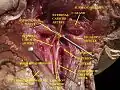

Superior thyroid artery Muscles, arteries and nerves of neck.Newborn dissection.

Muscles, arteries and nerves of neck.Newborn dissection. Muscles, nerves and arteries of neck.Deep dissection. Anterior view.

Muscles, nerves and arteries of neck.Deep dissection. Anterior view.